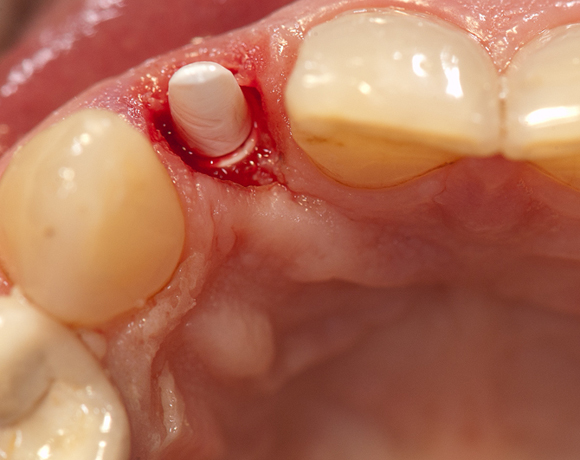

Im vorliegenden Patientenfall musste der Zahn 22 nach erfolgloser Endodontie entfernt werden. Die Nachbarzähne waren kariesfrei, es wurde eine Marylandbrücke (eine Brücke mit zwei Flügelchen, die palatinal an den Nachbarzähnen verklebt werden) oder ein Implantat besprochen. Die Patientin hat sich für ein Vollkeramikimplantat entschieden. In der Diashow wird der operative Eingriff bis zur fertigen Krone gezeigt. Die Einheilzeit betrug drei Monate.